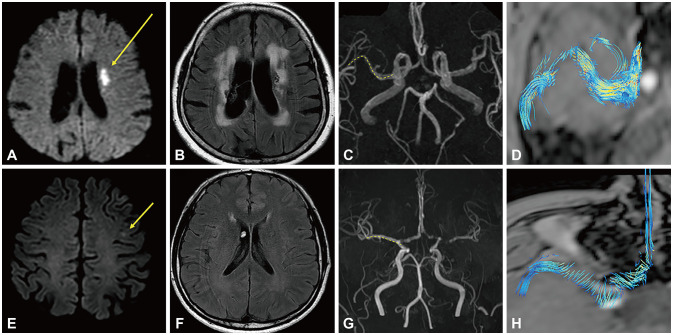

Methods: This study enrolled consecutive patients with acute ischemic stroke in the MCA territory who underwent high-resolution vessel wall magnetic resonance imaging and four-dimensional flow magnetic resonance imaging in accordance with the protocol of Kyung Hee University Hospital. Patients were categorized into two groups based on the burden of pre-existing cSVD in the hemisphere contralateral to the stroke lesion: those with a modified burden score of 0-4 (low cSVD burden) and those with a modified burden score of 5-7 (high cSVD burden). The vascular geometry (straight, U-shaped, or inverted-U- and S-shaped) and wall shear stress (WSS) measured at five different points in the contralesional MCA were compared between the two burden groups.

Results: This study included 145 patients with cSVD: 109 with a low burden and 36 with a high burden. A low cSVD burden was correlated with a U- or inverted-U-shaped MCA (p< 0.001). A high cSVD burden was associated with an S-shaped MCA (reference U- or inverted U-shaped MCA: odds ratio [OR]=8.653, 95% confidence interval [CI]=2.789-26.843, p<0.001), and with an increased maximum WSS at the second quintile point (OR=1.109, 95% CI=1.005-1.225, p=0.040) and elevated variability (standard deviation: OR=1.759, 95% CI=1.277-2.423, p=0.001).

Conclusions: A tortuous MCA along with an increased WSS magnitude and variability were independently associated with a high cSVD burden.